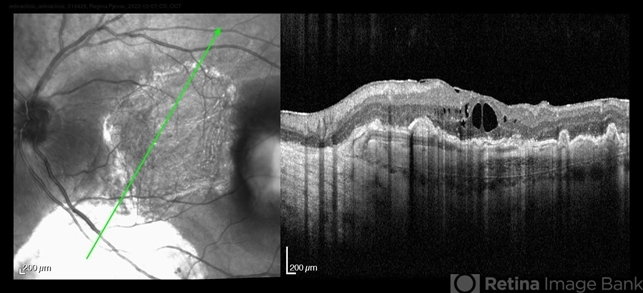

- wet age-related macular degeneration (wet AMD), neovascular age-related macular degeneration (AMD), pars plana vitrectomy (PPV)

- Postoperative period of RPE-transplantation in a patient with neovascular AMD after RPE tear.